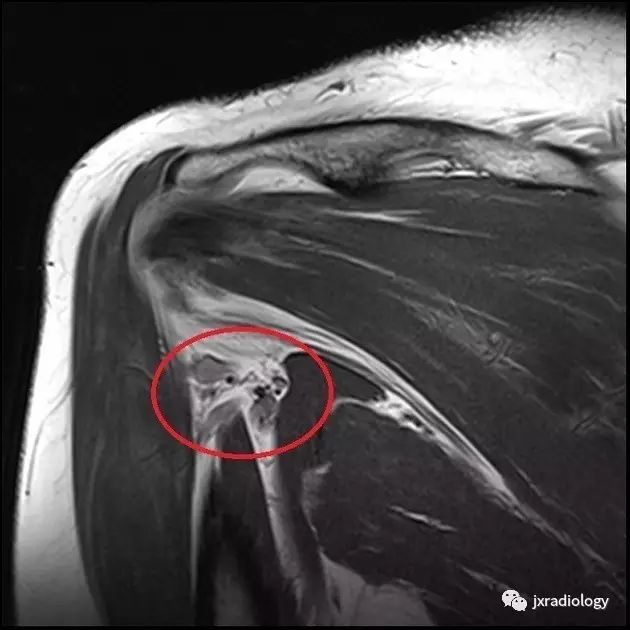

MRI is the investigation of choice, demonstrating atrophy +/- fatty infiltration in the teres minor and/or deltoid muscle. Literature review has shown varying proportions of deltoid and teres minor involvement.

MRI是首选的检查,表现为小圆肌和/或三角肌的萎缩+/-脂肪浸润。文献综述显示不同程度的三角肌和小圆肌的不同程度的受累。

MR Arthrogram showing a typical inferior paralabral cyst associated with a labral tear, causing QSS

MRI Scan showing atrophy of Teres Minor(小圆肌萎缩)